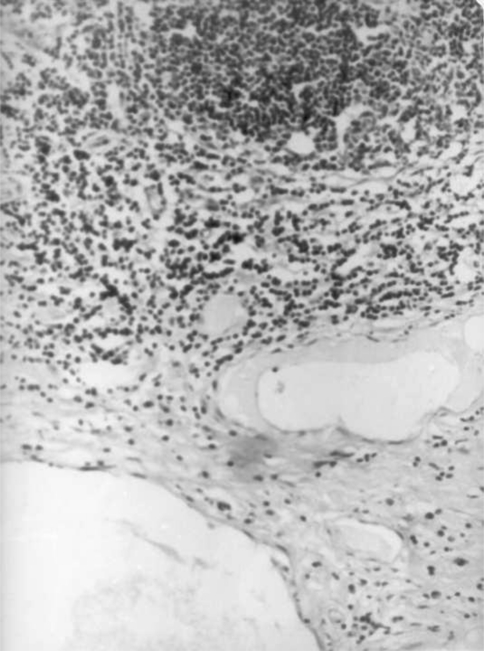

On microscopic examination, the mass was seen to be lined by hyperplastic stratified squamous epithelium (Fig. 3). Stroma was lose and edematous with multiple haphazardly arranged dilated lymphatic channels (Fig. 4) with lymphoid follicles in the intervening areas (Fig. 5).

Fig. 4.

Dilated lymphatic channels (H and E staining, ×400)